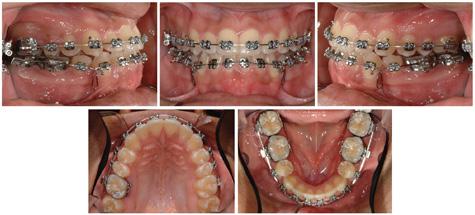

Maximum intercuspation occurred following an anterior functional shift of the mandible and then vertical bite closure. The molar and canine relationship is Class III bilaterally, obviously worse in centric occlusion compared to centric relation. The INITIAL occlusal photographs (Figure 2) show mild maxillary anterior crowding, undersized and unusual shaped second premolars, and no apparent Class III compensation. A similar amount of crowding is seen in the mandibular arch, however, the incisors exhibit some visual Class III compensation.

.018 traditional twin brackets were bonded to all of the teeth except for the mandibular molars, which were banded in anticipation of using a stiff rectangular stainless steel closing loop arch wire. Round nickel titanium arch wires were used for initial alignment, followed by rectangular arch wires of the same material. A 16 x 22 TMA arch wire was placed in the maxilla, along with a 16 x 22 SS closing loop arch wire in the mandible. Progress photos (Figure 4) were obtained at the conclusion of mandibular space closure. It is apparent at this time that there has been some loss of leveling, excess crown convergence at the extraction sites, and the need for improving the mandibular second premolar occlusion. Therefore, finishing included, dropping back to a 16 x 22 NiTi arch wire in the mandible, moving to a stiffer 16 x 22 SS arch wire in the maxilla, and adding triangular vertical elastics between the maxillary canines and mandibular canines/second premolars for settling of the occlusion. Total time in treatment was 19 months.

The FINAL intraoral photographs (Figure 6) highlight well aligned teeth, Class I canine occlusion bilaterally, and ideal overjet and overbite. Gingival revision of tooth #4 may be beneficial in the future if there is a delay in passive eruption following rotational correction of this maxillary right second premolar. Tooth #13 is more attractive.